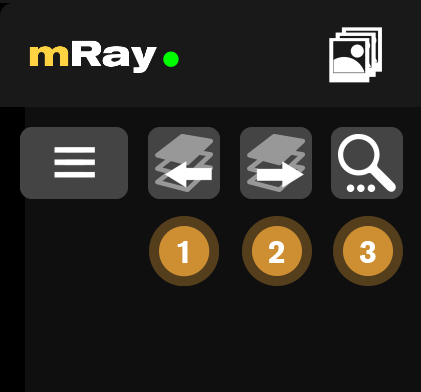

10.1. Series buttons

The series buttons only appear when there is another series in the current study.

-

Go to the previous series in the study.

-

Go to the next series in the study.

-

Search for associated studies